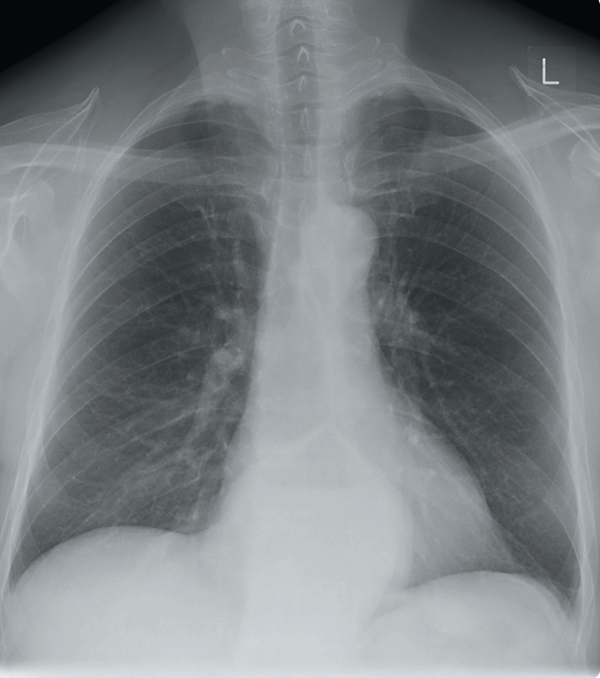

Un hombre de 54 años se presenta a la sala de emergencias con dificultad respiratoria aguda. Tiene antecedentes de enfermedad arterial isquémica y un historial de 20 paquetes-año de tabaquismo. En el examen físico, está afebril, con saturaciones del 90% en aire. La frecuencia cardíaca es de 100 lpm y la frecuencia respiratoria de 22. Se observa matidez y estertores inspiratorios en ambas zonas bajas. La presión yugular está elevada 4 cm. Se realiza una radiografía de tórax para buscar edema pulmonar.

La radiografía muestra características de insuficiencia cardíaca (cardiomegalia, opacificación intersticial, desvío venoso en los lóbulos superiores y pequeños derrames pleurales).

Se deben realizar análisis de electrolitos y función renal (U/Es) para evaluar la función renal, así como un hemograma (FBC) para detectar cualquier anemia asociada. Un electrocardiograma (ECG) sería útil para buscar posibles cambios eléctricos nuevos. Una ecocardiografía (ECHO) permitiría evaluar la función del ventrículo izquierdo.

El paciente debe ser tratado por edema pulmonar agudo/insuficiencia cardíaca. Una radiografía de tórax de seguimiento puede usarse para monitorear la respuesta al tratamiento.